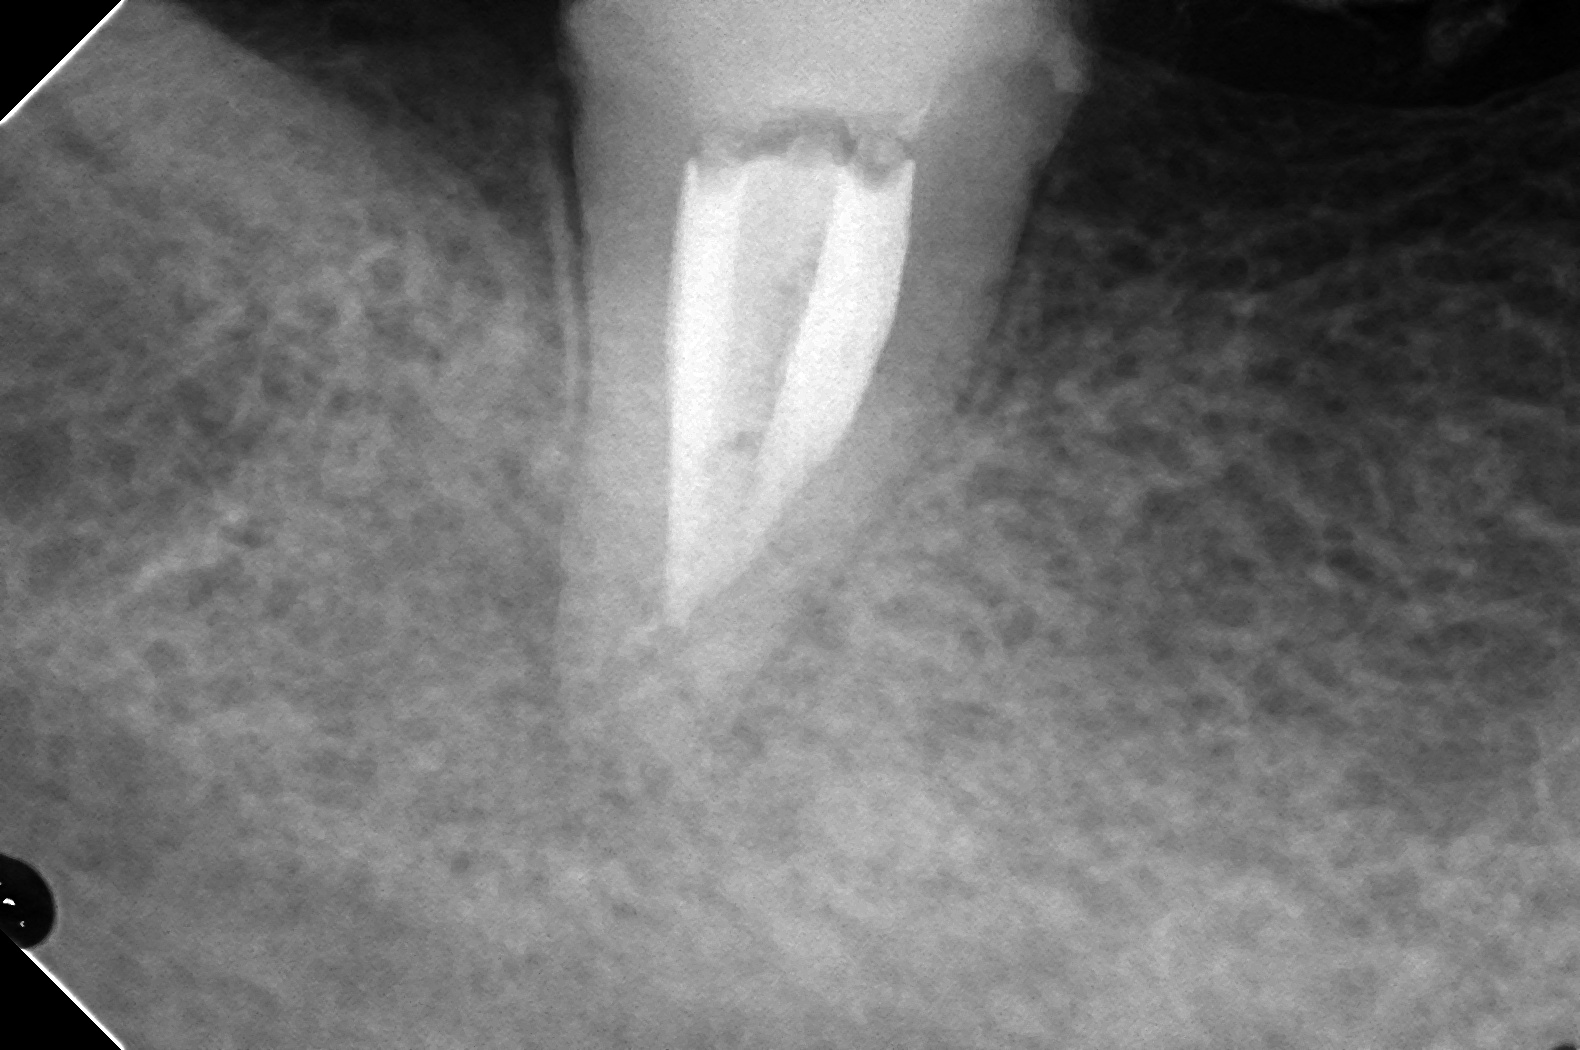

DB118547_161026170652(調整後)根充時

近心にもしっかり骨できました(^^♪